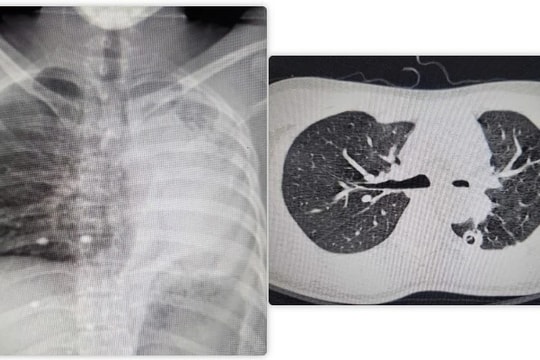

Phẫu thuật thành công hồi sinh lá phổi xẹp hoàn toàn cho nam bệnh nhân

27/03/2025 09:00

Sau 4 giờ phẫu thuật cân não, các bác sĩ Bệnh viện Bạch Mai đã tái tạo thành công đường thở, giúp hồi sinh lá phổi xẹp hoàn toàn cho nam người bệnh bằng kỹ thuật nội soi tiên tiến.